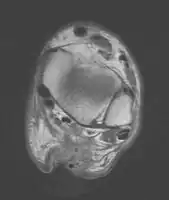

Musculoskeletal ultrasonography can be used to determine the tendon thickness, character, and presence of a tear. It works by sending extremely high frequencies of sound through the body. Some of these sounds are reflected back off the spaces between interstitial fluid and soft tissue or bone. These reflected images can be analyzed and computed into an image. These images are captured in real time and can be very helpful in detecting movement of the tendon and visualising possible injuries or tears. This device makes it very easy to spot structural damages to soft tissues, and consistent method of detecting this type of injury. This imaging modality is inexpensive, involves no ionizing radiation and, in the hands of skilled ultrasonographers, may be very reliable.

Transverse plane/Achilles tendon rupture

Achilles tendon rupture seen on ultrasound. Note discontinuity over several centimeters (red line). No fracture or avulsion (radiograph).